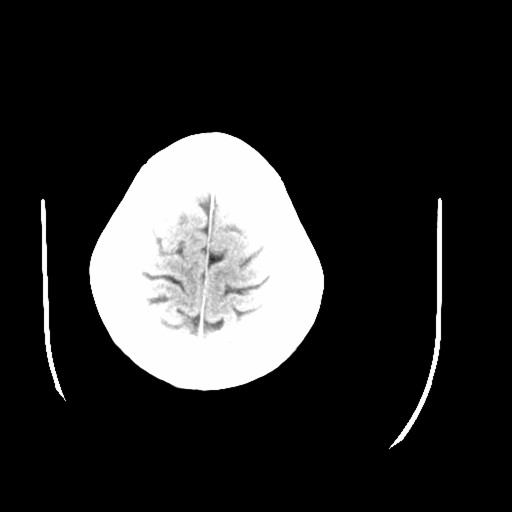

标题: CT16233:女,44岁,智障多年,现感头痛 [打印本页]

标题: CT16233:女,44岁,智障多年,现感头痛

1)小脑萎缩。2)小脑蚓部发育不良。

小脑萎缩征,原因待定.